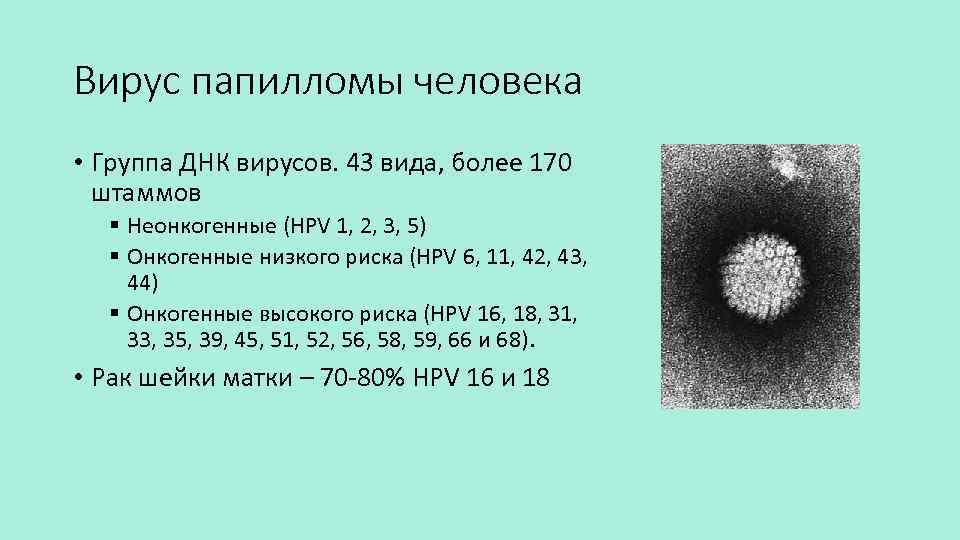

Всего на сегодняшний день зарегистрировано около 170 типов папилломавируса. Большая их часть никак не влияет на здоровье. Отдельные штаммы провоцируют появление кожных наростов того или иного вида.

И есть опасные для человека типы ВПЧ, способные вызывать предраковые состояния. Клетки эпителия, измененные онкогенными штаммами, могут малигнизироваться – превращаться со временем в злокачественные опухоли.

Вульгарные бородавки и нитевидные папилломы на теле вызываются типами ВПЧ с низким онкогенным риском. Они перерождаются в рак не чаще, чем здоровые участки, и представляют собой преимущественно косметический дефект.

Появление новообразований, которые называются папилломами или висячими родинками, вызвано проникновением в организм вируса папилломы человека (ВПЧ), различными штаммами которого заражено большинство людей на планете. Когда новообразование формируется и растет, человек обычно не испытывает боли или какого-либо дискомфорта. При этом выросшие папилломы выглядят как сосочки на поверхности кожи, держащиеся на тонкой ножке, и из-за своей выпуклости легко травмируются мочалкой, расческой, украшениями или одеждой. Новообразования могут появляться не только на коже, но и на слизистых. Особенно неблагоприятными считаются те, что растут в подмышках и паховой области. В результате травмирования папиллома может воспалиться и кровоточить, а при повторяющемся повреждении может даже переродиться в злокачественное новообразование.

Обязательному устранению подлежат бородавки (кондиломы) на интимных органах. Они вызываются потенциально опасными штаммами ВПЧ и склонны при хроническом течении перерождаться в рак. К тому же эти наросты передаются половым путем, значит, угроза здоровью налицо.